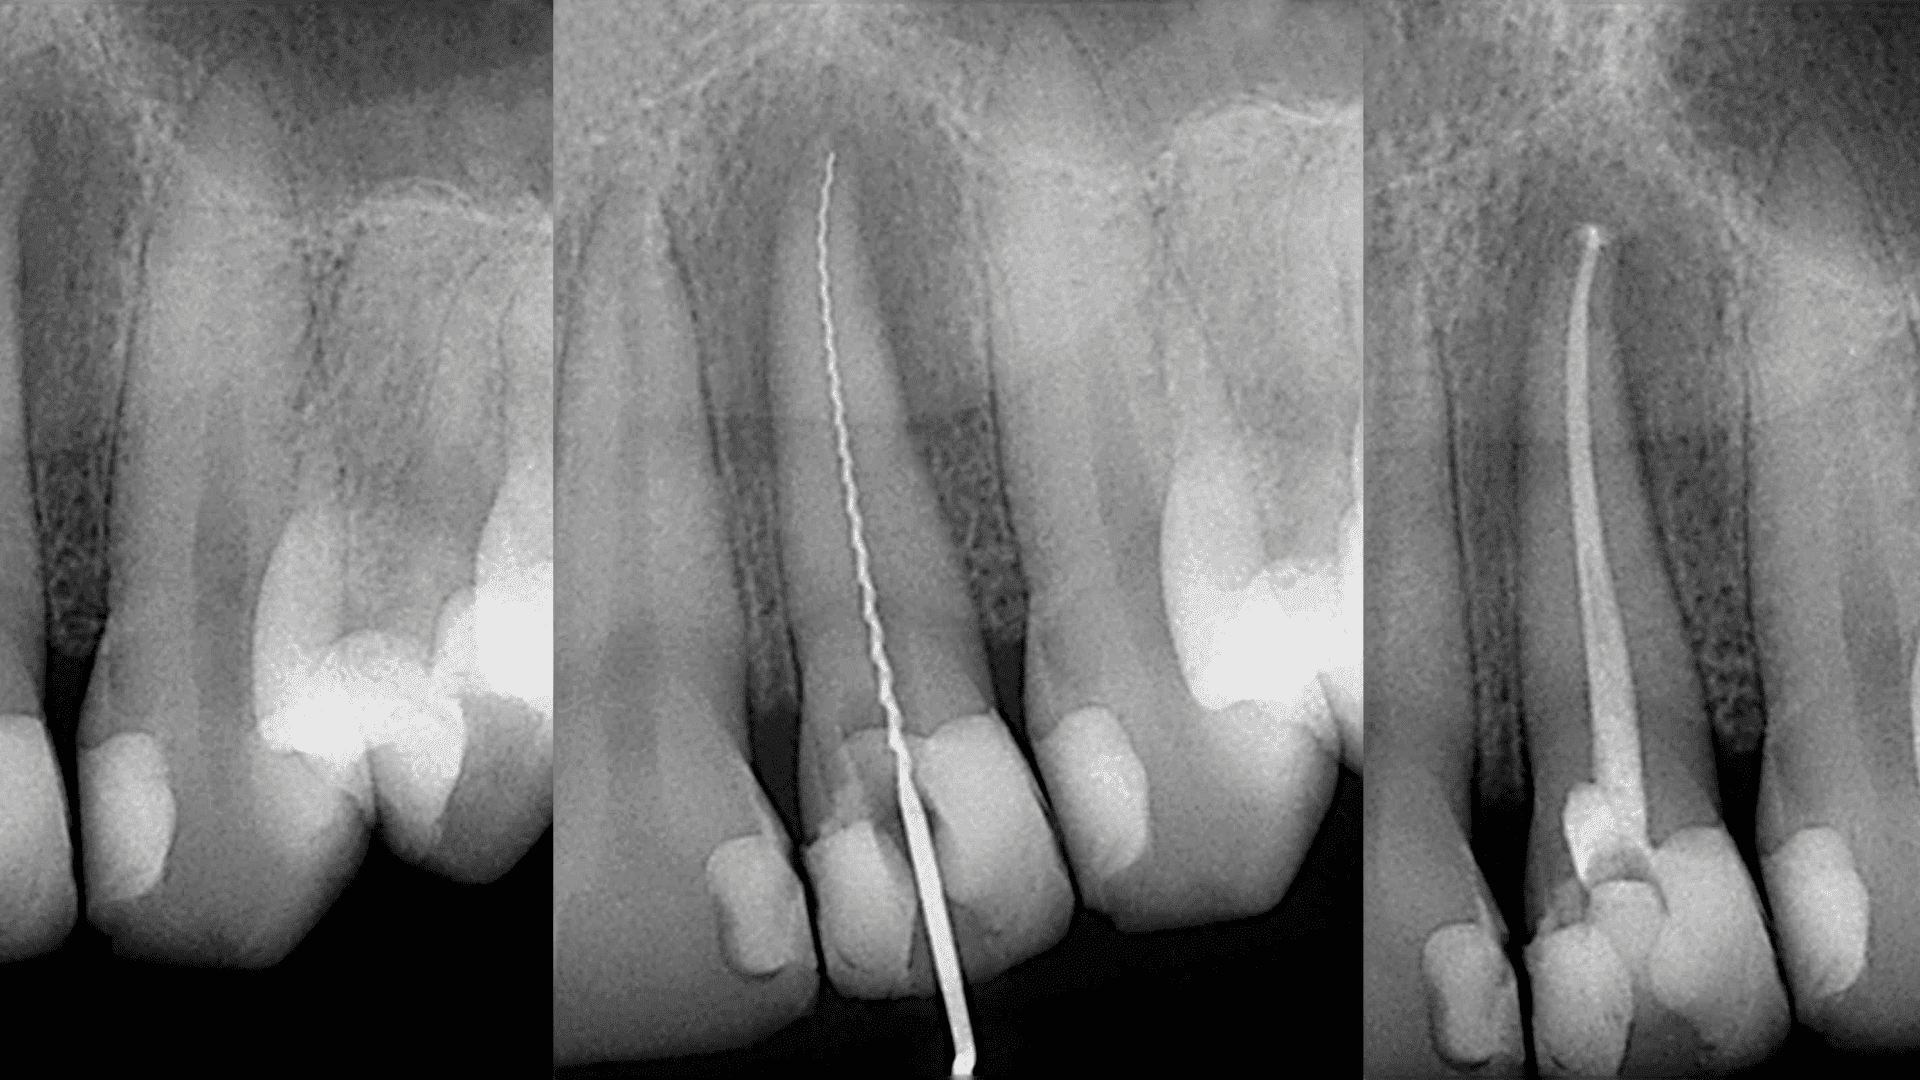

Skorzystaj z precyzyjnej diagnostyki, jaką oferuje zdjęcie punktowe RTG w naszej klinice. Ta metoda pozwala na szczegółowe zbadanie konkretnego obszaru zęba lub korzenia, umożliwiając szybką i dokładną diagnozę.